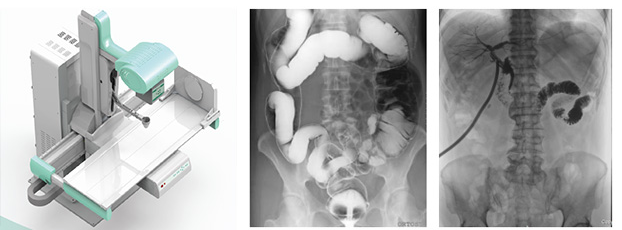

動態DR是一款多功能DR,能夠數字拍片、數字透視、數字造影。

動態DR是使用多功能動態數字化探測器成像的直接數字化X射線攝影系統。

動態DR具有大幅面(17inch×17inch)高清拍片、大幅面(17inch×17inch)透視、視頻實時保存回放、可視化造影、毫秒級點片等基礎功能,以及斷層融合、數字減影等延展性功能。

普愛醫療作為全球較好的數字影像設備供應商,專注于DR系列產品的技術創新,在全國范圍內率先推出動態DR。以其“一機多用”集常規拍片、胃腸、透視、造影于一體的多功能作用深受放射科臨床醫生的鐘意。